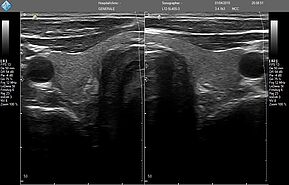

- MicrUs Pro-L40S (линейный, 5-12 МГц, 40 мм)

MicrUs Pro-L40N (линейный, 5-12 МГц, 40 мм, производительная версия)

MicrUs Pro-C60S (конвексній, 2-5 МГц, R60 мм)

ЗДЕСЬ Вы можете посмотреть реальные кинопетли с аппарата УЗИ MicrUs Pro.